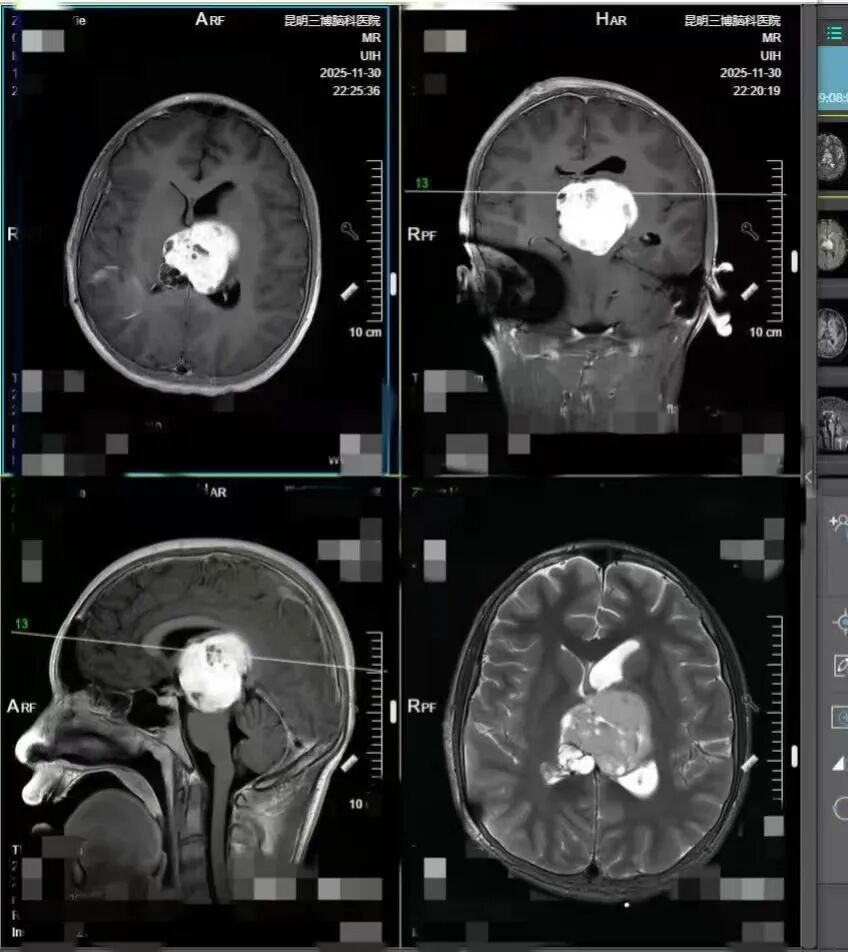

检查结果赫然显示:大脑第三脑室占位性病变,初步考虑为生殖细胞瘤,且肿瘤已伴出血,体积十分巨大,压迫着整个大脑中枢。确诊的消息如同惊雷,而小熙的病情更是急转直下——短短三天,他的手脚开始无力,连饭碗都端不稳。11 月 20 日,小熙被紧急转往昆明接受治疗,医院立即启动脱水、放疗等对症处理,可死神的脚步并未放缓。治疗期间,小熙的意识逐渐模糊,最终陷入昏迷,癫痫发作更是频繁且难以控制。

入院后的加急检查,结果比预想的更棘手。「肿瘤位置极差,跨越了中脑、丘脑、第三脑室和双侧脑室,考虑是混合生殖细胞瘤,不仅体积大、血运丰富,已经出现出血情况。」张宏伟教授拿着检查报告,向小熙母亲详细解释,「这么大的肿瘤压迫着关键脑组织,才引发了昏迷、癫痫、脑积水、颅内压增高等一系列并发症。其实孩子两个月前就该出现症状了,比如头疼、视物模糊、耳鸣、反应迟钝等就是典型信号。」

惋惜之余,张宏伟教授迅速给出判断:「如果能早一个月发现并干预,还能有手术切除的机会。但现在病情进展太快,已经错过了手术时机。放疗起效需要一定的时间,孩子的情况根本等不起,当下唯一的出路,就是利用肿瘤对化疗的敏感度,先通过精准化疗缩小肿瘤,让孩子恢复意识,才能为后续治疗争取空间。」